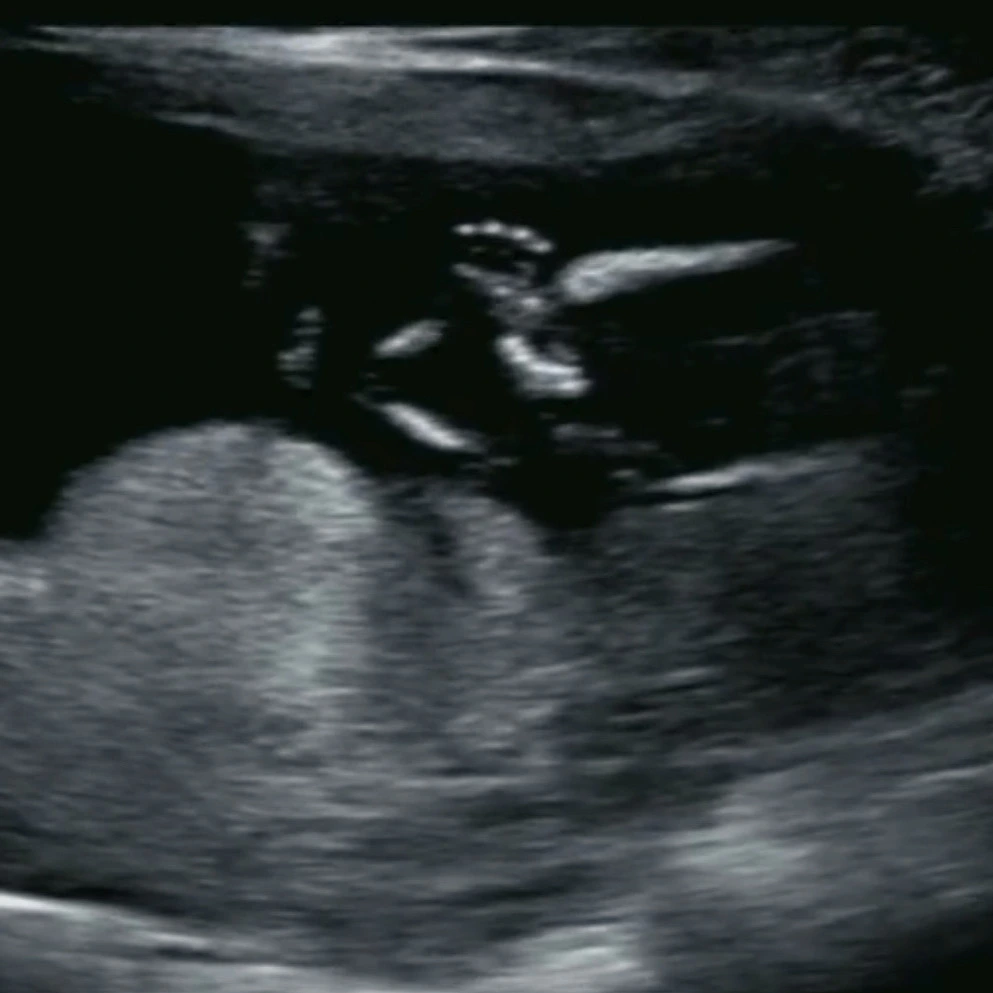

이제 어느덧 13주 3일, 병원에서는 이제 유산 확률이 1% 이하인 시기에 접어들었다고 한다.